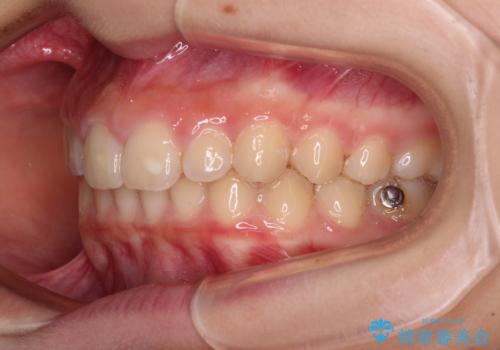

- ヨーロッパにてインビザライン矯正を始めたものの、日本に転居することになり、治療の継続を希望して来院された患者様です。

治療計画に無理がなく、現地担当医と速やかに連絡が取れるとのことで、インビザライン社での転医手続きを行い、継続して治療を行うこととしました。

舌の突出癖により、上下前歯が非接触となっていたため、トレーニングを徹底的に指導し、安定した咬み合わせにより終了させることができました。